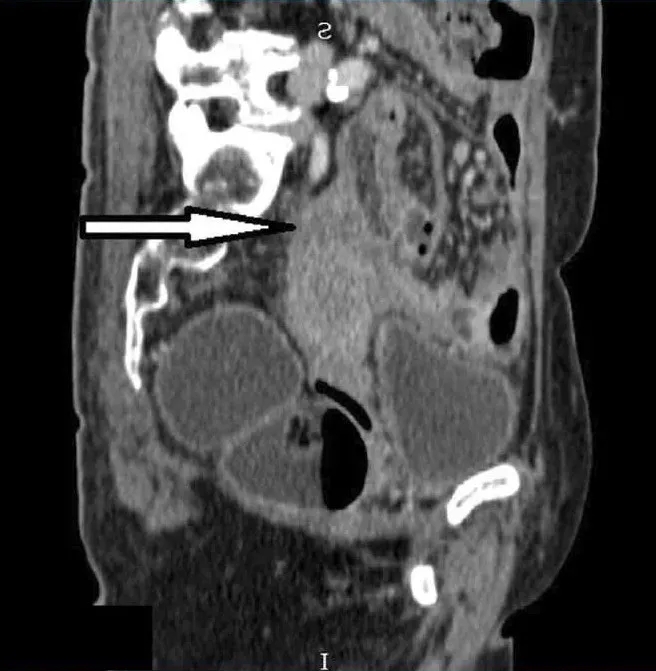

在关节炎出现六个月后,她因腹痛主诉到一家私人医院就诊,接受含网膜活检的小型开腹手术。网膜病理学检查发现II级卵巢浆液性囊腺癌的转移灶沉积。她被诊断为IIIc期卵巢癌,开始新辅助化疗,方案为卡铂(AUC=5,d1)+紫杉醇(80 mg/m2,d1,d8,d15),每21天一周期,共6个周期。SSZ停药。经过三个周期的化疗后,患者出现了新的呼吸道症状。胸部/腹部重复CT显示左侧肺尖后部肿块,双侧肺多发结节,子宫底区域有边界不清的低密度肿块(图3、4)。随后进行了硬质支气管镜检查,发现左上肺叶有一个带蒂肿瘤,几乎完全闭塞了远端左主支气管。肿瘤活检显示为具有肉瘤样特征的恶性肿瘤。

图4. 矢状面计算机断层扫描显示:子宫底肿块与子宫下方的分界差(箭头)